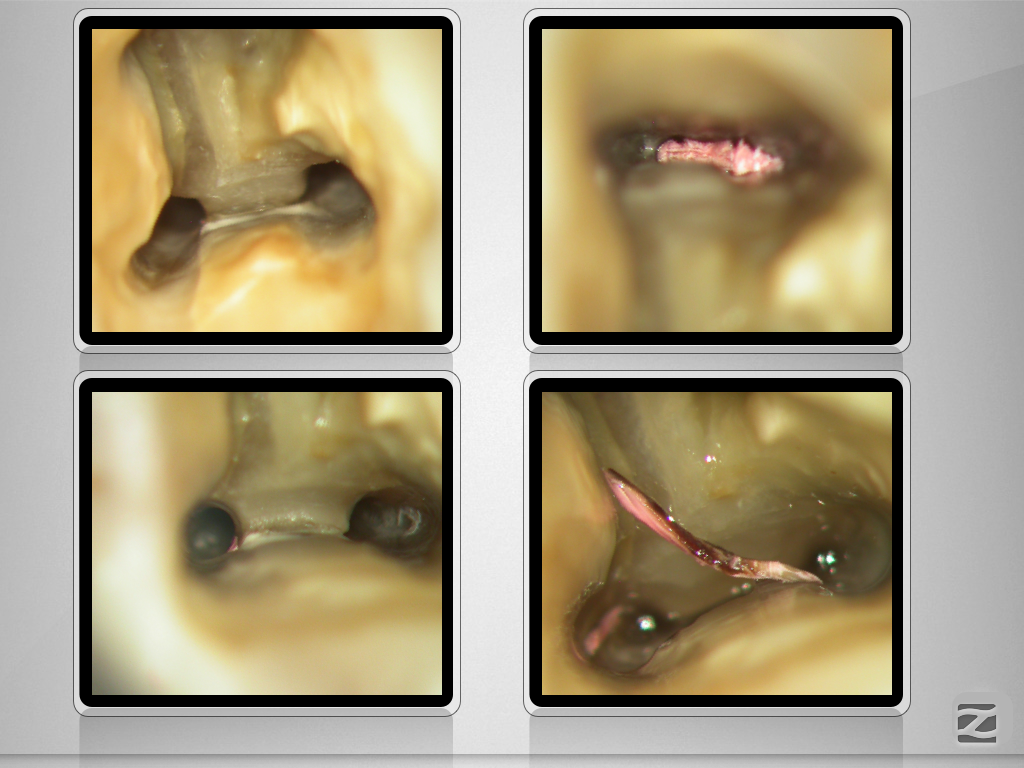

37D.013

Ausgedehnte apikale Lyse